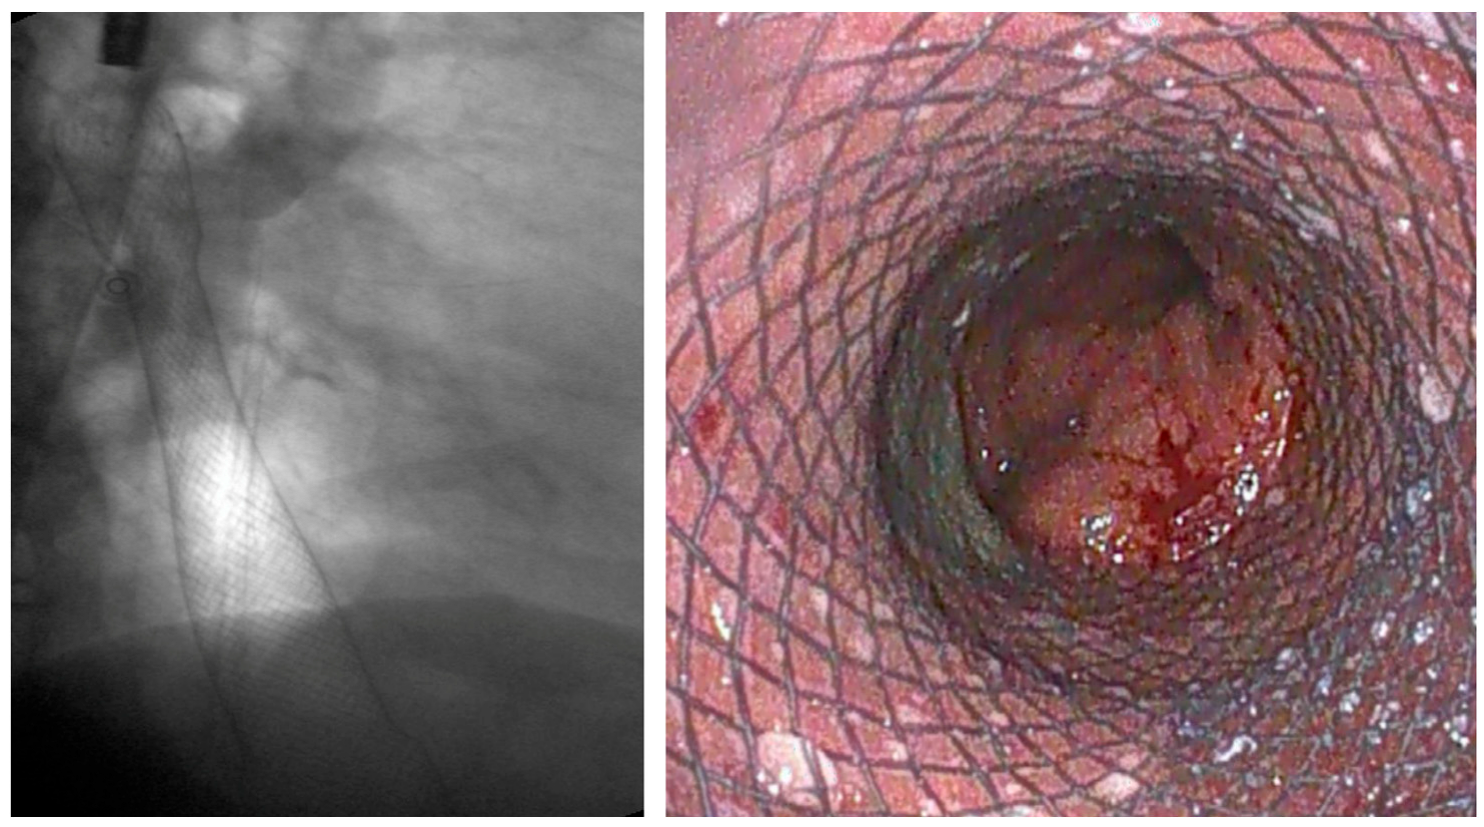

3.3. Benign Strictures

3.3.1. Role of Stent

Indication and Mechanism of Action

Efficacy and Adverse Events